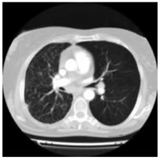

| Types | Original Image | Embedded Image | Noise Image | Output |

|---|---|---|---|---|

| CT | ![]() | ![]() | ![]() | ![]() |